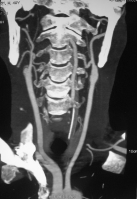

Hình 3.2a. Minh họa tắc động mạch cảnh trong hai bên – ca đầu tiên. Bệnh nhân TAK, nam, 49 tuổi, nhồi máu não phần trước (nhánh nông trên) động mạch não trước phải, với nhồi máu cũ ranh giới sau trái, tắc động mạch cảnh trong hai bên, với bàng hệ thấy được là hai nhánh nhỏ từ động mạch cảnh ngoài mỗi bên nối vào đoạn xương đá của động mạch cảnh trong (mũi tên). Động mạch não giữa phải (cùng bên) hẹp nặng đầu đoạn M2

Có 3 bệnh nhân (2,5%) tắc hoàn toàn động mạch cảnh trong đối bên, nghĩa là tắc động mạch cảnh trong cả hai bên (Hình 3.2 a,b). Ba mươi bệnh nhân (24,8%) có động mạch cảnh trong đối bên hoàn toàn bình thường. Còn lại đại đa số bệnh nhân có xơ vữa hẹp một phần động mạch cảnh trong đối bên (n=88; 72,7%, trong đó 7,4% hẹp nặng, 65,3% hẹp nhẹ).